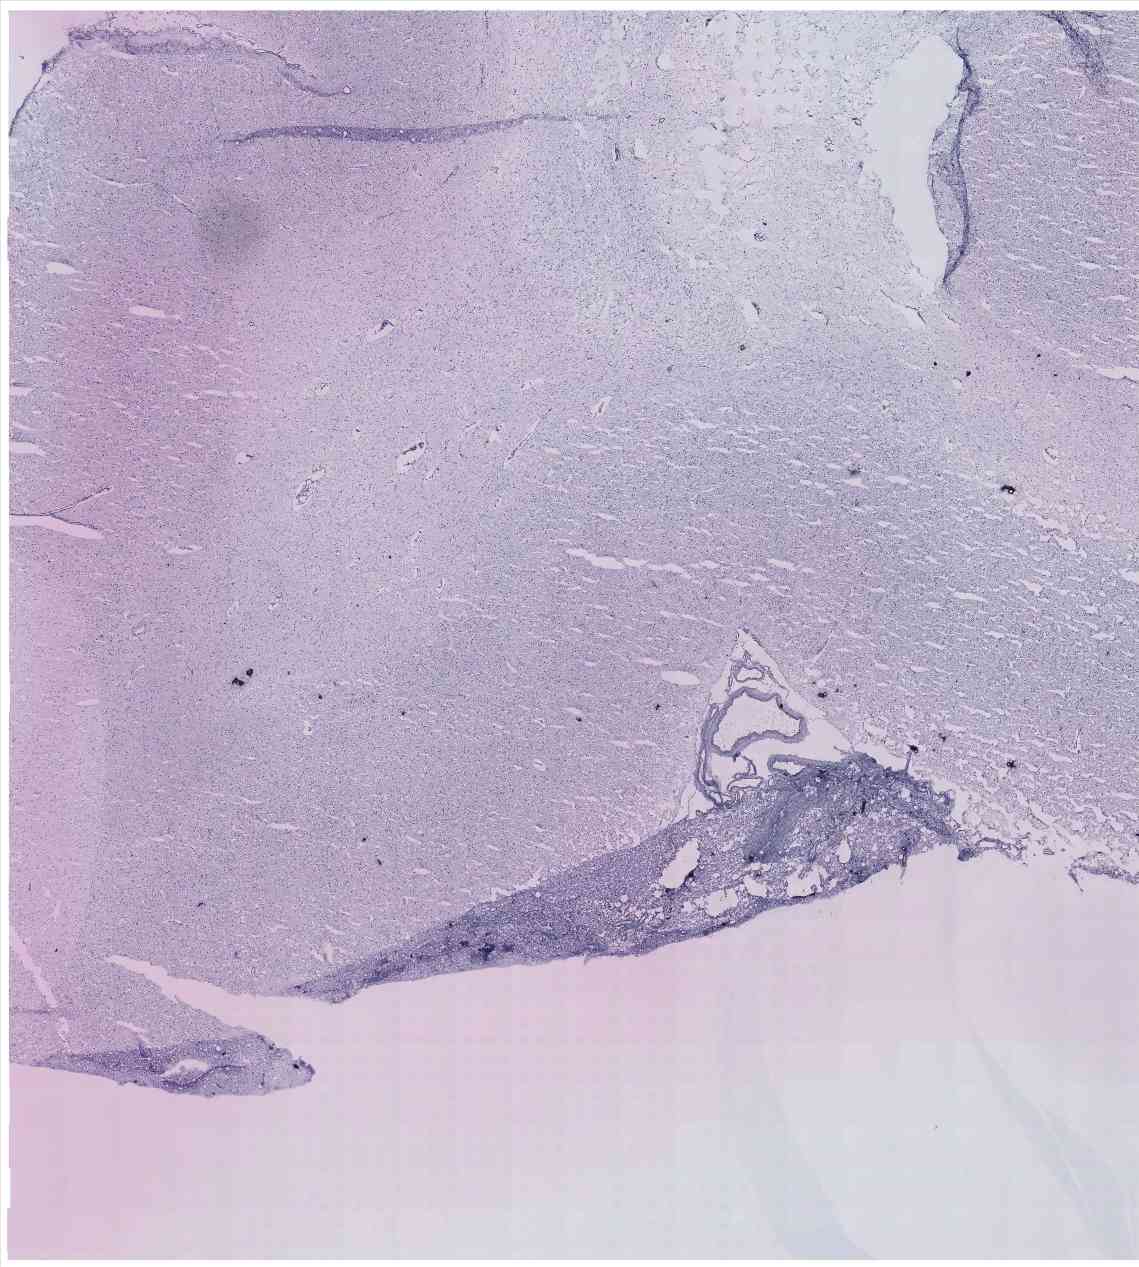

Chip 016 Well E1